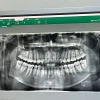

이 흔들려서 치과 갔는데 개같이 멸망

치과 드디어 갔는데

이 안 흔들리고 충치도 없이 말짱하다고 감기래요

스케일링이나 받고 왔음